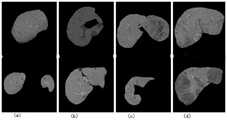

图7是本发明实施例提供的第一阶段肝脏识别模型对不同复杂场景下的肝脏分割结果示意图;7 is a schematic diagram of a liver segmentation result under different complex scenarios by a first-stage liver identification model provided by an embodiment of the present invention;

图中:(a)肝脏被其它器官截断成两部分;(b)含有肝裂的情形;(c)含有弥漫型肝病情形;(d)肝脏内含有非肝脏区域。In the figure: (a) the liver is truncated into two parts by other organs; (b) the case with liver fissure; (c) the case with diffuse liver disease; (d) the non-liver region in the liver.

实施例一,模型第一阶段对于CT影像中肝脏的识别。随机挑选模型在复杂场景下对肝脏的分割结果,如图7所示,模型能够很好的处理识别难度非常大的各类情形,如:图7(a)原图肝脏被其它器官截断成两部分;图7(b)肝脏中含有肝裂的情形;图7(c)肝脏中含有弥漫型病变的情形;图7(d)肝脏内含有非肝脏区域。Example 1: The first stage of the model is for the identification of the liver in the CT image. The segmentation results of the liver by the randomly selected model in complex scenes are shown in Figure 7. The model can handle various situations that are very difficult to identify, such as: Figure 7(a) The original liver is truncated into two parts by other organs. Part; Fig. 7(b) liver with fissures; Fig. 7(c) liver with diffuse lesions; Fig. 7(d) liver with non-liver areas.